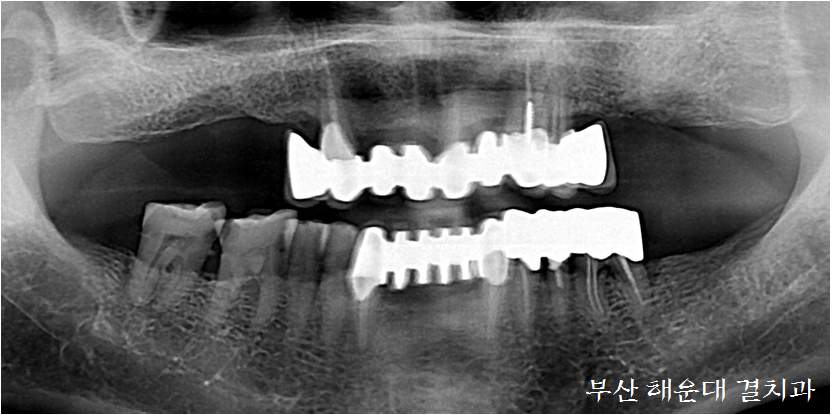

05. 임플란트 보철물 제작

상악의 경우 임플란트와 치조골 사이의 결합까지 3-4개월 이상의 치유기간을 거쳐 최종 보철물을 완성하게 됩니다.